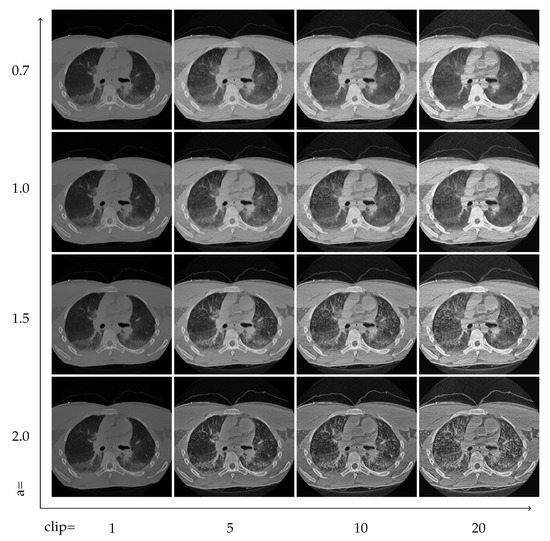

The effect of the two control parameters, the exponent of the power-law, and the contrast limit is visualized in Figure 7 and Figure 8. Faster decreasing weights further enhance the local features, including noise. The contrast limit from CLAHE effectively regulates this issue.

Figure 7.

The effect of the weighting function and clipping. Rows from top to bottom have a = 0.7, 1.0, 1.5, 2.0, respectively, and the clip limits in the columns from left to right are 1, 5, 10 and 20, using units where N is the number of histogram bins.

5.2. Locality and Clipping Limits

The two control parameters strongly affect the quality of the resulting images. However, finding the right balance can strongly depend on the visualization goal. Higher exponents mean stronger local contrast enhancement, but can also enhance noise. The contrast limit works against the distortions, but also limits the achievable feature amplification. Two image grids in Figure 7 and Figure 8 demonstrate these issues.